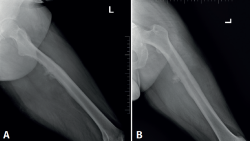

Cincuenta días tras el accidente se realizó fusión lumbar instrumentada L4-L5 con inserción de dispositivo intersomático por vía transforaminal derecha. En el segundo día postoperatorio presentó empeoramiento del dolor, objetivándose en la tomografía computarizada (Figura 2) malposición del tornillo L5 izquierdo que invadía el canal. Se reintervino a los 5 días corrigiendo el trayecto del tornillo. Sin embargo, persistió el dolor. La revaluación del caso, sumada a los hallazgos de EMG, motivó estudios complementarios de pierna y trayecto ciático (Figuras 3 y 4), detectándose una masa tumoral en el fémur izquierdo compatible con sarcoma fusocelular.

Figura 2. Tomografía computarizada lumbar postoperatoria en corte axial. Tornillo pedicular izquierdo de L5 mal posicionado, con violación de la pared medial del pedículo e invasión parcial del canal vertebral.